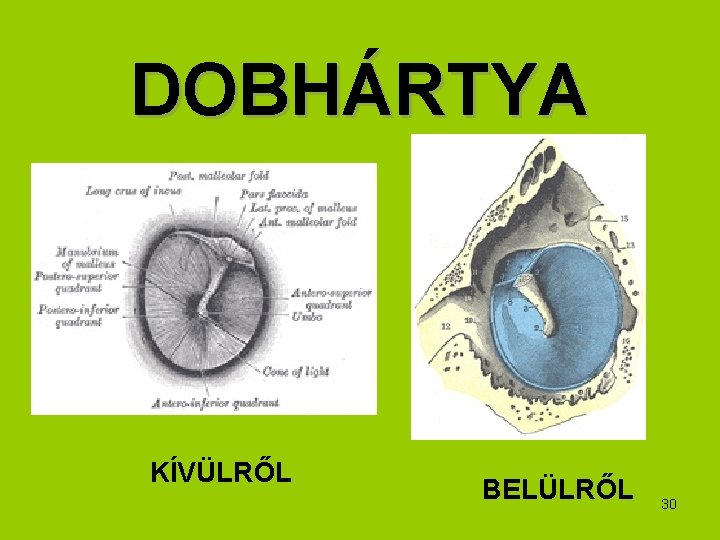

DOBHÁRTYA KÍVÜLRŐL BELÜLRŐL 30